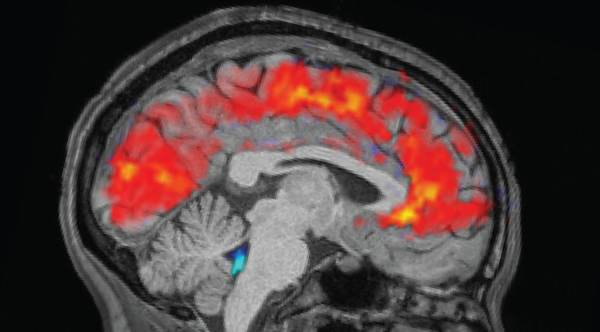

In a 2023 report issued in the journal Alcohol, scientists came upon that the outer layer of the brains of individuals with alcohol use ailment, which can lessen as a consequence of alcohol misuse, regained its density after roughly seven months of abstaining from alcoholic drinks. Before abstaining, the study participants were ingesting approximately 13 drinks a day over 12 months, Vice detailed.

The advantageous consequences of abstaining surfaced even earlier, however.

“Our group and other academics have perceived prompt restoration over two to four weeks of abstinence, for brain capacity in assorted areas across the brain, in those diagnosed with an alcohol use disorder,” Timothy Durazzo, head study writer and professor of psychiatry and behavioral sciences at Stanford University, communicated to Vice.